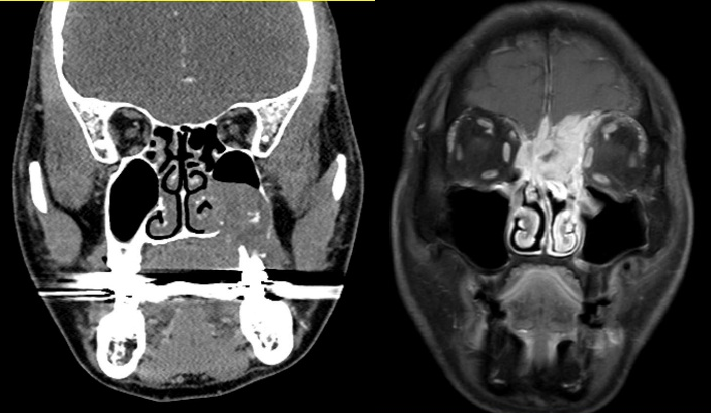

두경부암의 진단의 경우에는 크게 신체검사와 영상검사를 통해서 진단하게 됩니다. 신체검사의 기본은 이비인후과적 내시경 검사이며 이때 환자가 호소하는 증상과 연관된 부위를 중심으로 증상을 유발할 수 있는 모든 부위를 내시경으로 자세히 검사하게 됩니다. 두경부암의 경우 경부임파선 전이가 드물지 않기 때문에 양손을 이용하여 전문의가 시행하는 경부 촉진검사 또한 매우 중요합니다. 원발부위로 의심되는 병변이 발견될 경우에는 접근이 쉬운 부위의 경우 외래에서 조직검사를 바로 시행하며, 후두암이나 하인두암 같이 외래에서 조직검사가 용이하지 않은 부위는 조직검사 및 병변의 진행정도 평가를 위해서 전신마취를 해야 할 수 있습니다. 또한 경부전이 여부를 정밀검사 하기 위하여 경부 전산화단층 촬영(CT) 및 초음파 검사를 시행하게 됩니다. 마지막으로 진행된 두경부암의 경우에는 최종 치료 방침을 결정하고 치료를 시작하기 전에 원격전이가 없는지 여부 확인을 위해서 PET 검사를 추가로 시행하게 됩니다.

비부비동암: 상악동암, 비강암